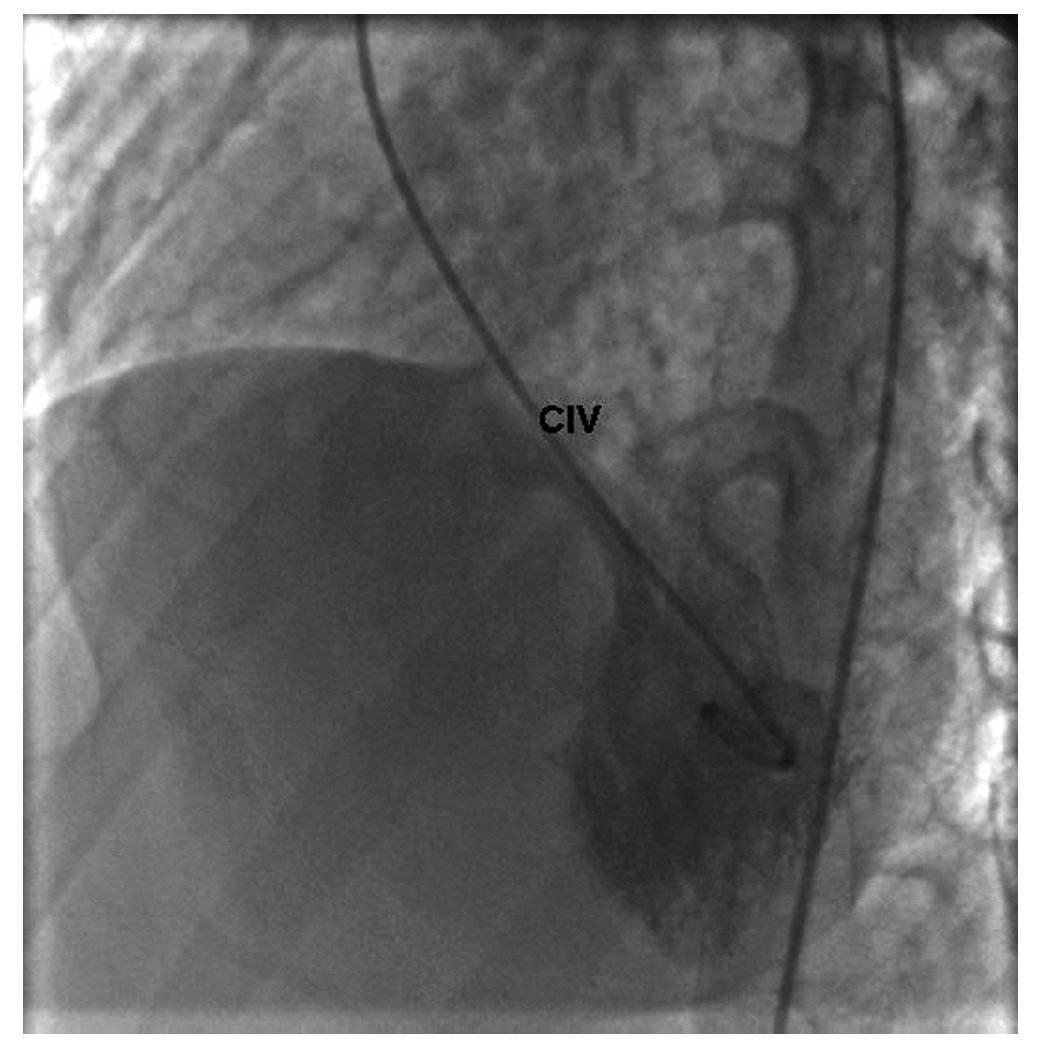

Figura 4 Angiocardiograma en posición oblicua izquierda. Se observa el paso de medio de contraste del ventrículo izquierdo al derecho por la comunicación interventricular. La arteria coronaria derecha insinúa la dilatación del ventrículo derecho. CIV: comunicación interventricular.